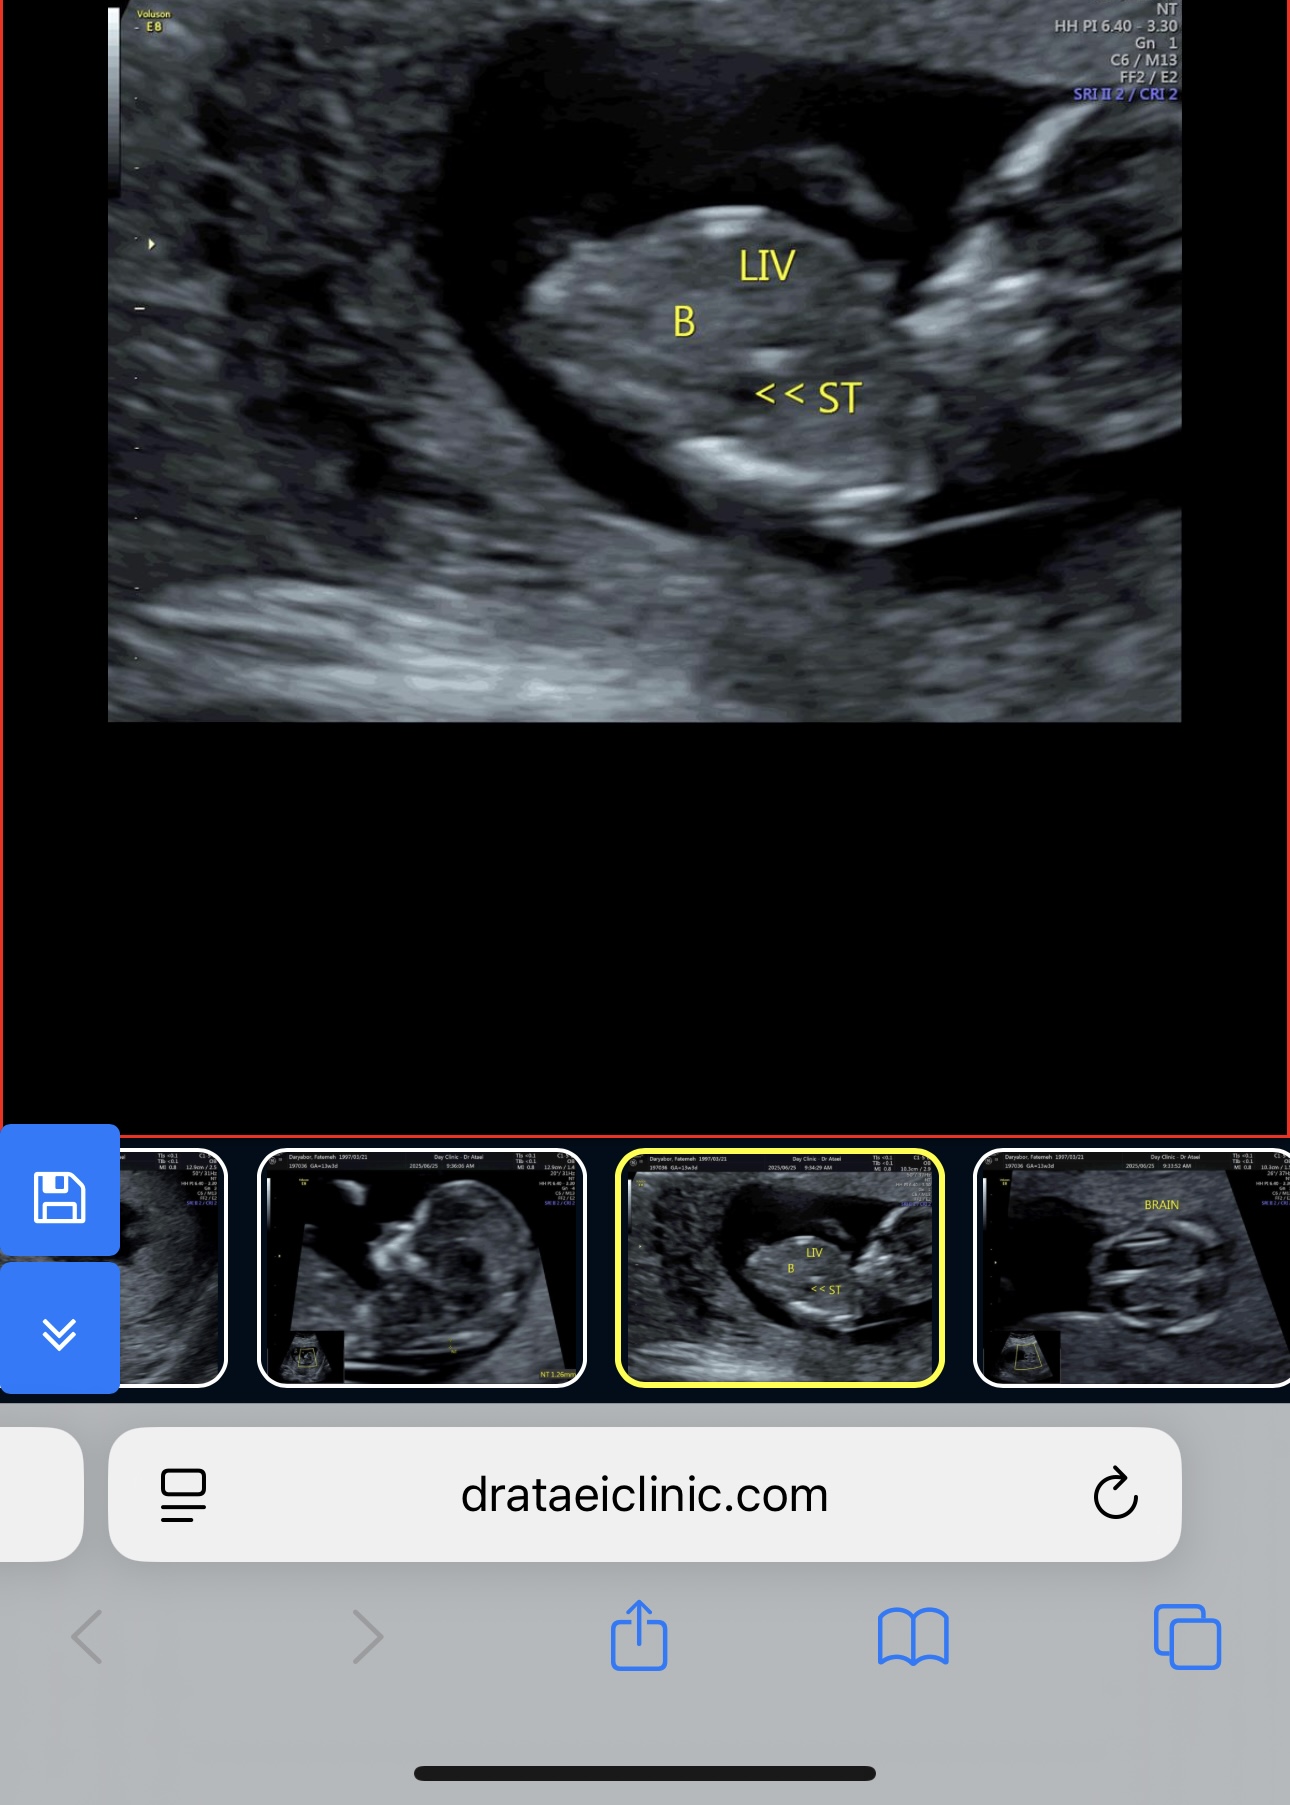

امروز رفتم انتی دادم خداروشکر همه چیز خوب بود

عکس های انتی رو الان میذارم ممنون میشم نظرتون رو بگید بهم